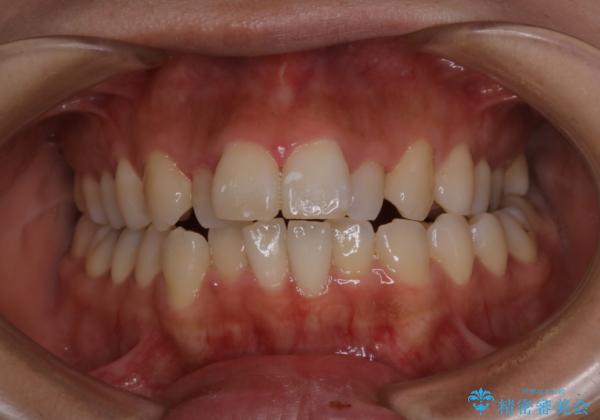

- 患者様

- 20代女性

- 矯正装置

- ワイヤー矯正 審美装置

- 治療期間

- 1年6ヶ月

- 治療回数

- 10-30回

- 費用(概算)

- 88万円費用は治療当時の料金となります